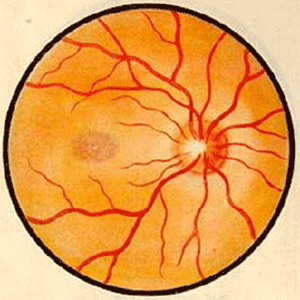

视神经病变